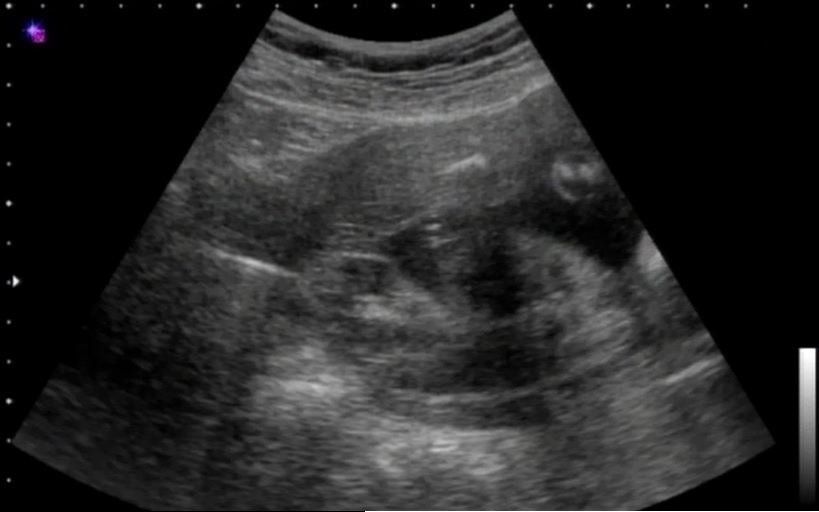

胎児 エコー 女の子 割れ目-エコー写真で男の子・女の子の性別の見分け方をみていきましょう。 女の子の特徴 木の葉型・コーヒー豆がみえる 週数が経つと外性器が形成され、股の部分に割れ目がエコーで見えるでしょう。 妊娠23週で女の子に変わった!!エコー写真あり そして妊娠6ヶ月、23週1日目に性別が覆ったエコー写真がこちら! 矢印の先に黒い一本の線があるの分かりますか? これが女の子の割れ目だそうです! 先生からは「結果女の子だったね~!女の子 で 確定

胎児 エコー 女の子 割れ目 エコー写真からわかる男の子、女の子の判別。ダウン症や口唇 女の子のエコー写真の特徴 女の子の判別する場合も男の子の判別と同様に、胎児の両足の間を見性別 エコー 女の子 割れ目のお悩みや相談は、先輩ママからのアドバイス満載なウィメンズパークで解決!ベネッセコーポレーションが運営する、全国170万人以上の女性が集まるサイトです。